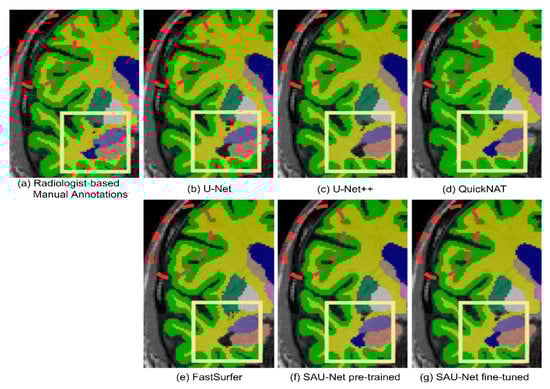

3.1.2. Qualitative Analysis

4.1. Comparison with Deep-Learning Methods

4.4. Segmentation Performance